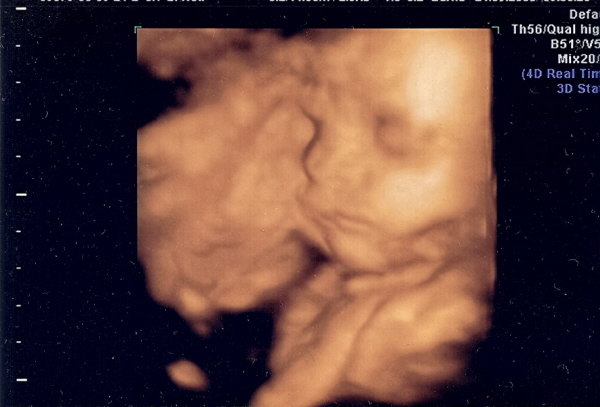

Felrakom és is a 4d-s képet a csajszimról :lol: nagyon nagy élmény volt elmenni és háromnegyed órán keresztül csak őt nézni :D :D Kép

Nagyon szép a 4d-s kép! :)

Bessy nagyon szép a te kis csajszid is :) , szerintem is olyan nagy élmény ilyenkor nézegetni őket, áldom aki kitalálta a 4d-t. Ti hol voltatok amúgy, hogy ilyen sokáig nézhettétek? Pesten? Csini harisnya megjött? :D Diétázás hogy megy?

Nagyon édes babátok van!Hol voltatok UH-n?Elhiszem,hogy élvezted a mozizást,én is imádtam nézni,ahogy forgolódik,nyújtózkodik a pocimban.Látod ezt édesanyáink még nem élhették át!Milyen jó,hogy ennyit fejlődött a technika!

Igen, Pesten voltunk a 4d Genesisben. Ti a Gólyafészekben voltatok ugye? Ott mennyi ideig nézték?